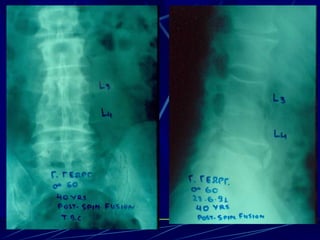

Φυματίωση της σπονδυλικής στήλης